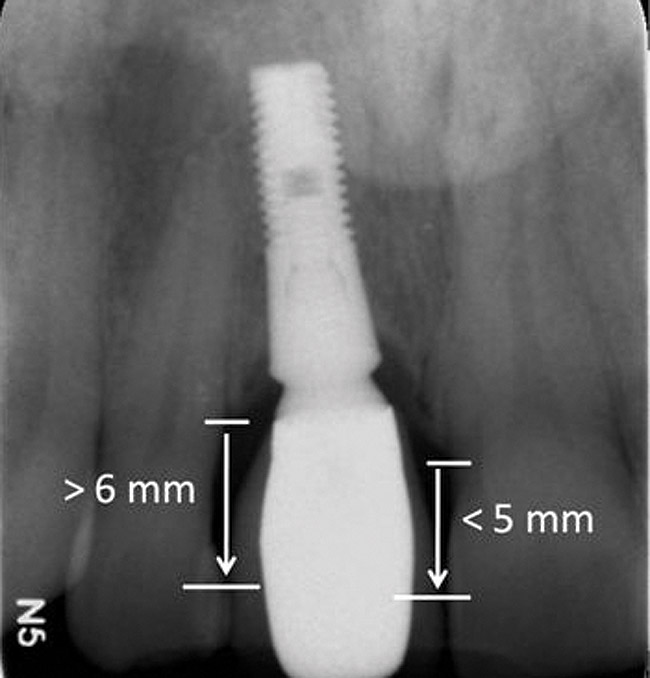

Figure 4  Characterization of the interproximal bone and tooth contacts: A periapical radiograph assists in measuring the distance from bone crest to the adjacent tooth contact points for missing tooth No. 8. The mesial bone crest to the adjacent tooth contact distance is < 5 mm, while the distal bone crest to adjacent tooth contact distance is > 6 mm (Fig 4). One-year following implant placement, conservation of these dimensions is revealed (Fig 5). The clinical photograph (Fig 6) of the lateral incisor adjacent to tooth No. 8 implant crown demonstrates that the absence of distal interproximal (papilla) fill related to the observed bone crest to contact distance exceeds 6 mm.

Figure 4

Figure 5  Characterization of the interproximal bone and tooth contacts: A periapical radiograph assists in measuring the distance from bone crest to the adjacent tooth contact points for missing tooth No. 8. The mesial bone crest to the adjacent tooth contact distance is < 5 mm, while the distal bone crest to adjacent tooth contact distance is > 6 mm (Fig 4). One-year following implant placement, conservation of these dimensions is revealed (Fig 5). The clinical photograph (Fig 6) of the lateral incisor adjacent to tooth No. 8 implant crown demonstrates that the absence of distal interproximal (papilla) fill related to the observed bone crest to contact distance exceeds 6 mm.

Figure 5